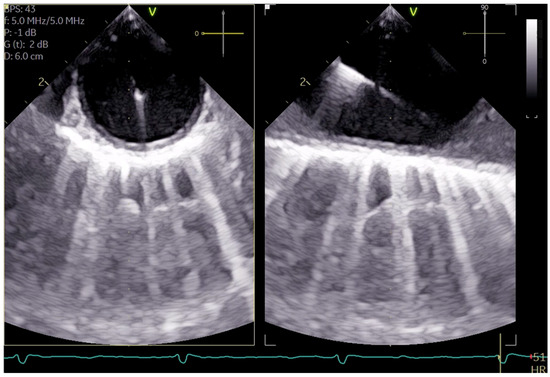

The cannulation of peripheral vessels for the purpose of establishing cardiopulmonary bypass (CPB) in minimal invasive cardiac surgery requires a meticulous approach. This is necessary in order to facilitate optimal redirection of blood flow. The femoral artery and vein, as well as the right internal jugular vein, are commonly employed vessels for cannulation [9]. These vessels offer accessible peripheral entry points for the insertion of cannulas, allowing for the efficient initiation of CPB while minimizing trauma to surrounding tissues [20]. Furthermore, advancements in surgical techniques have enabled the utilization of peripheral vessels such as the axillary artery, providing alternative cannulation sites that further enhance the minimally invasive nature of the procedure. This is achieved by potentially beneficial antegrade flow during cardiac procedures, which is currently under investigation [21]. By carefully selecting and cannulating these vessels, surgeons can effectively establish CPB with precision and safety, thereby facilitating successful outcomes in minimal invasive cardiac surgery. For femoral veins, a lengthy cannula (Bio-Medicus 23/25 FR multistage femoral venous cannula, Medtronic, Minneapolis, MN, USA) is introduced into the inferior vena cava, primarily via the right femoral vein, with echocardiographic guidance (refer to Videos S1 and S2). According to the established protocol, the guidewires are visualized. The venous wire and cannula are depicted through TEE in the midesophageal bicaval view (see Figure 1a,b). The arterial wire is visualized in the descending aortic short-axis (SAX) and long-axis (LAX) views (see Figure 2 and Video S3). The exclusion of malposition such as in the hepatic vein or interatrial septum perforation is carried out.

Figure 1.

(a) shows the midesophageal bicaval view with the venous wire via the inferior vena cava into the superior vena cava; (b) shows the midesophageal bicaval view, with the cannula passing through the right atrium.